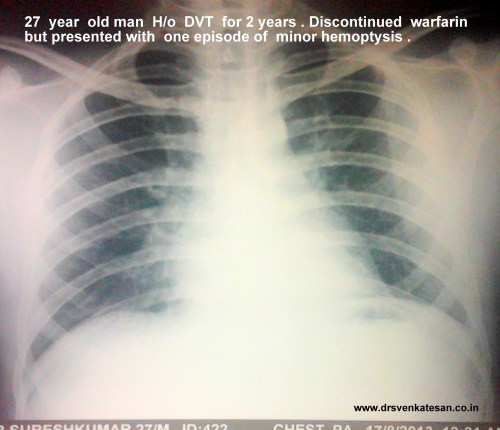

A 25 year man ,  hotel  manager  who had a documented DVT , since 2011 was on tablet warfarin . He discontinued  the drug by sheer miscommunication as he was told he should stop the  drug  beyond INR 3 by his general practitioner.He stopped it permanently  instead of titrating the dose of warfain .Six months later he landed  in August 2013 with an episode of minor hemoptysis . Clincally he was normal .His lower limbs were fine.

He was investigated and  his image file showed .

pulmonary embolism  3  total occlusion of LPA

pulmonary embolism total occlusion of LPA

Living with one lung

• He is comfortable with one lung function (Akin to  Pneumonectomy )

• His saturation was 100 % at room air

• Pulse -80/mt .BP 110/80mmhg

• His physical activity  did  not show any significant limitation (At worst class 2)

One of the cardiac surgery consultant wanted to do pulmonary embolectomy and endarteriectomy .

In fact , he was admitted in the critical care unit driven by the dramatic CT images.

One enthusiastic cardiologist wanted  thrombus aspiration and pig tail catheter based thrombolytic  irrigation within LPA !

How did we manage ?

• The risk of major vascular surgery was considered high in an absolutely asymptomatic individual .

• Intervention was considered too adventurous.

• He was  put on oral anticoagulant with target  INR 2.5-3.(After a 1 week Heparin overlap)

• We hope the thrombotic CTO will open up gradually but for surely .As the power of  natural lytic  molecules should not be underestimated as we have witnessed in LV and LA clot disappearing over months.

• However the option of putting IVC filter was strongly recommended for him , as he has only  functioning  lung  which  is threatened by a potential  embolus from DVT . The patient wanted to come back for IVC filter next month.

• He was also worked up for all those protein C, S,  Lieden mutation stuff.

• The patient was discharged in stable condition (By the way he  was never unstable either !)

* Meanwhile the hemoptysis  did not recur. CT scan showed a small wedge infarct in left lung that was in the healing mode.

Final message

This is a perfect example of  CTO of pulmonary artery being  managed conservatively* .We will let you know the follow up .